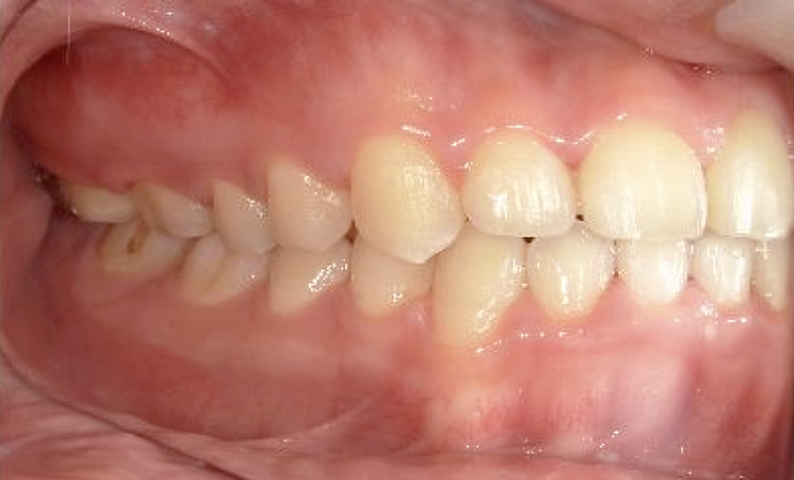

症例_024 上下顎の部分矯正

治療期間:13ヶ月金額:51万円+税女性前歯のガタガタ八重歯